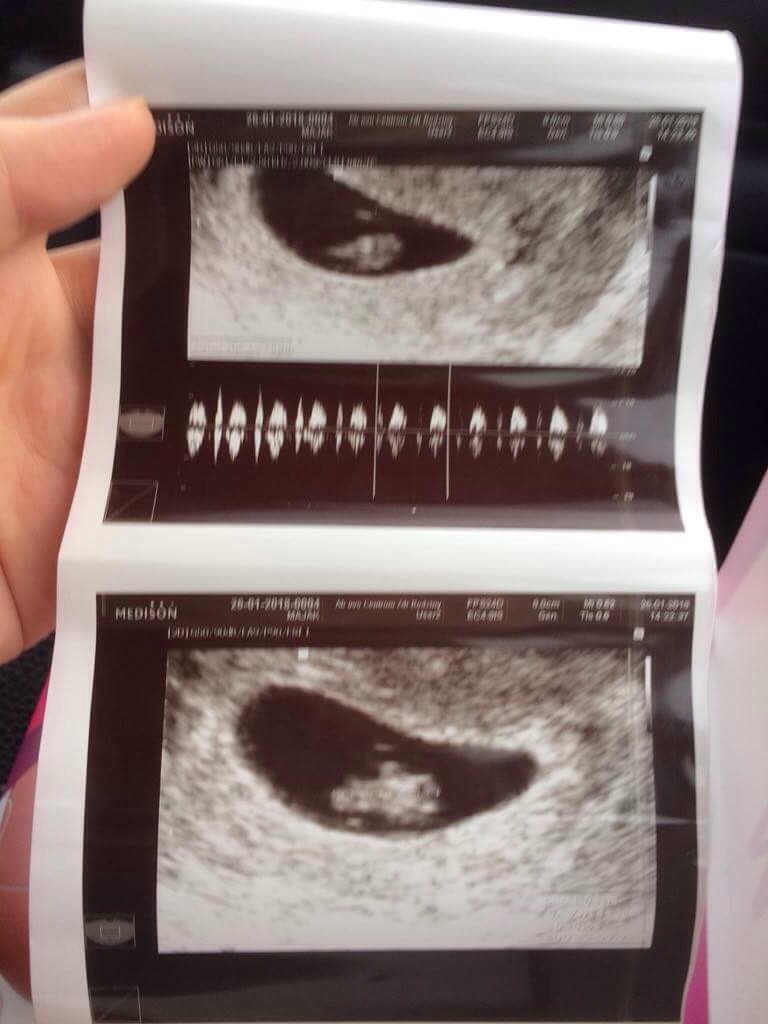

Cioteczki przedstawiam Wam mojego kropeczka [emoji7] bąbelek ma cały cm i serduszko bije 173/min [emoji173]️ pan dr nawet zrobił nam stereo piękny dźwięk usłyszeć bijące serduszko maluszka[emoji173]️[emoji173]️[emoji173]️poryczalam się na fotelu ze nie mogłam słowa wydusić. Małż wniebowzięty był przy usg i wszystko widział [emoji5][emoji5] następna wizyta za miesiąc [emoji4]

Wszystkim Wam życzę takich chwil oby jak najszybciej [emoji4]